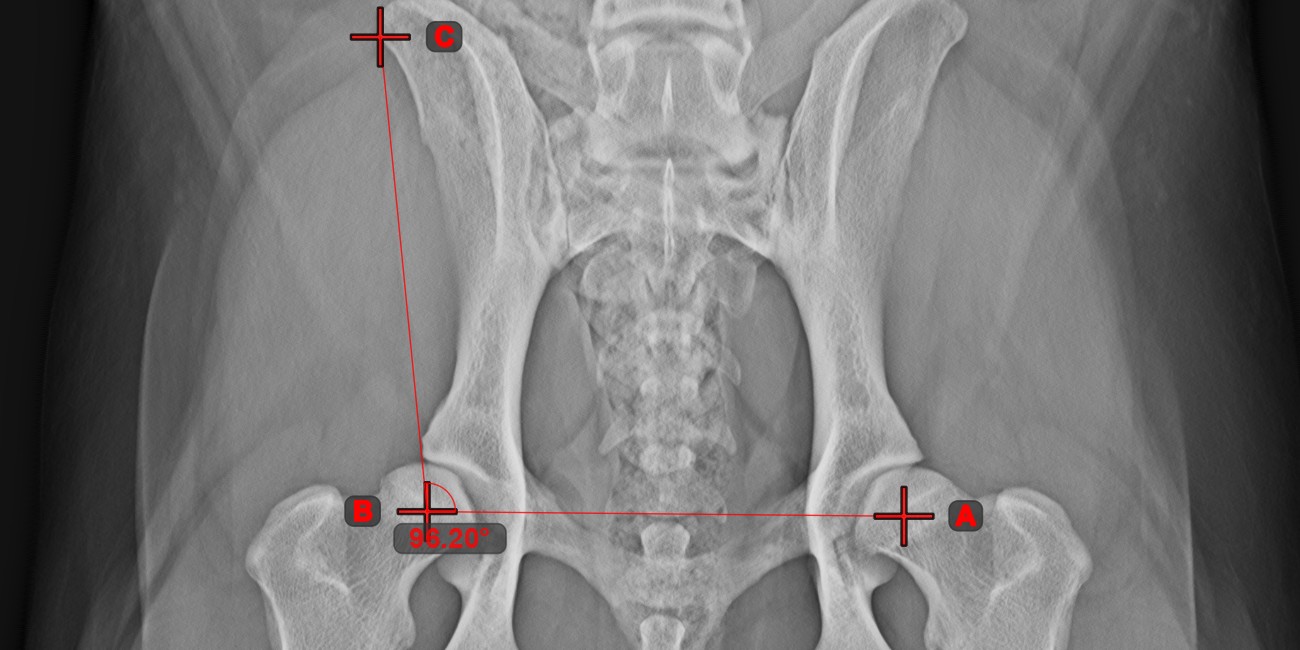

Angle of Lines¶

Select the tool from the left toolbar and assign it to one of the available mouse buttons. Start by selecting the first line from the ones already drawn on the scene, or place the start and end points to create the line. Follow the same steps for the second line of the measurement. The angle between the two lines will be automatically calculated.

Modify the start and end points of both lines by using the Select/Move Item

tool. The angle between the two lines will be automatically recalculated.

Angle from 3 Points¶

The Angle from 3 Points

tool is a simple and effective way to calculate an angle from just three points.

Start by selecting the tool from the left toolbar and assign it to one of the available mouse buttons. Place the start point of the initial side, the vertex, and the end point of the terminal side of the angle, or select the points from the scene. The sides of the angle will be automatically constructed, thus calculating the angle between the lines.